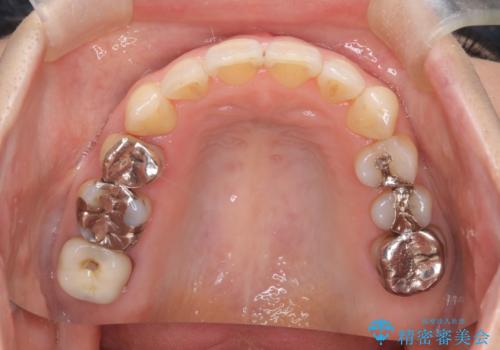

- 右上の八重歯(犬歯の突出)と、それに伴う歯並びのがたつきを主訴にご来院されました。精密検査の結果、八重歯を正しい位置に収めるためのスペースが大幅に不足していることが分かりました。

通常、矯正治療では4番目の歯を抜歯することが多いですが、今回は歯の状態や全体の噛み合わせのバランスを考慮し、右上5番(第二小臼歯)を抜歯してスペースを確保する計画を立案。装置には、周囲に気づかれずに治療を進めたいというご希望に合わせて、透明なマウスピース型のインビザラインを採用しました。

今回の治療では、右上5番の抜歯スペースを活用して八重歯(3番)を後方へ誘導しました。